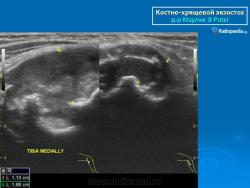

Костно-хрящевые экзостозы (остеохондрома).

Костно-хрящевые экзостозы